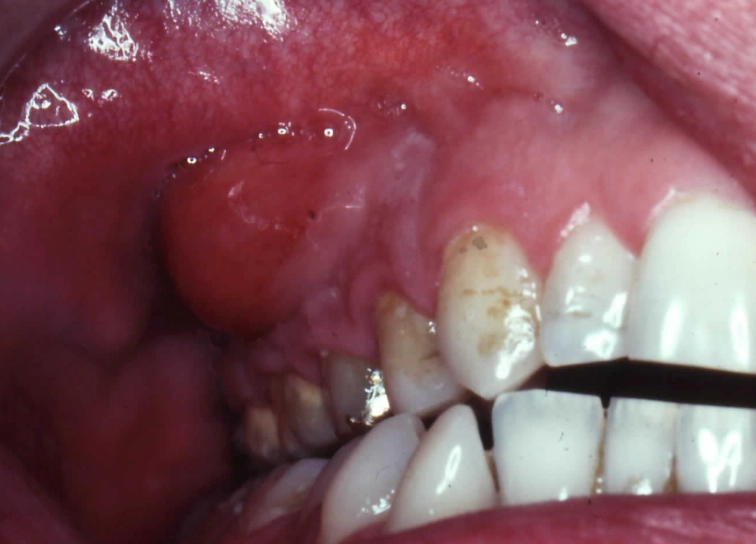

- Swelling in the Gums: Look in the mirror. Is there a pimple-like bump on the gum near the root of the painful tooth? Dentists call this a "parulis" or gum boil. It might be red, yellow at the tip, and it could ooze pus or blood if you press on it (though I don't recommend pressing on it). This is actually a drainage point for the abscess.

- Swelling in the Face or Jaw: This is when things get serious. The infection spreads from the bone into the softer tissues of your cheek, jawline, or under your tongue. The skin becomes tender, warm, and visibly puffy. The classic "chipmunk cheek" appearance.